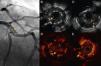

An 86-year-old woman with a history of severe three-vessel disease was treated in 2006 with a drug-eluting stent in the proximal left anterior descending artery. She was recently readmitted with an acute anterior infarction, coronary angiography showing a contrast defect in the left anterior descending artery (LAD) stent and a contrasting image outside suggestive of stent malapposition. OCT images showed extended stent malapposition, severe circumferential aneurysm with a diameter of 5 mm and abundant intraluminal thrombi. IVUS was used to better visualize the aneurysmal structure, and confirmed the lesion and thrombus image inside. Thrombus aspiration was not performed due to lack of the appropriate aspiration device. A 3.5 mm × 28 mm MGuard coated stent was implanted, with a good angiographic result (Figure 1).

(A) Coronary angiography of the left anterior descending artery (LAD) in right anterior oblique cranial view, showing an extensive intraluminal filling defect, multilobed, compatible with stent thrombosis (arrow). (B and C) Intravascular ultrasound (IVUS) images showing extensive stent strut malapposition (arrow), which appears to be coated with echogenic tissue that could correspond to adherent thrombus. (C) Extensive stent thrombosis (asterisk) and aneurysmal dilatation of the vessel outside the struts (arrow). (D and E) Optical coherence tomography (OCT) images at the same level as the previous IVUS, showing strut malapposition (arrow) with adherent platelet thrombus. (E) Extensive stent thrombosis (asterisk).